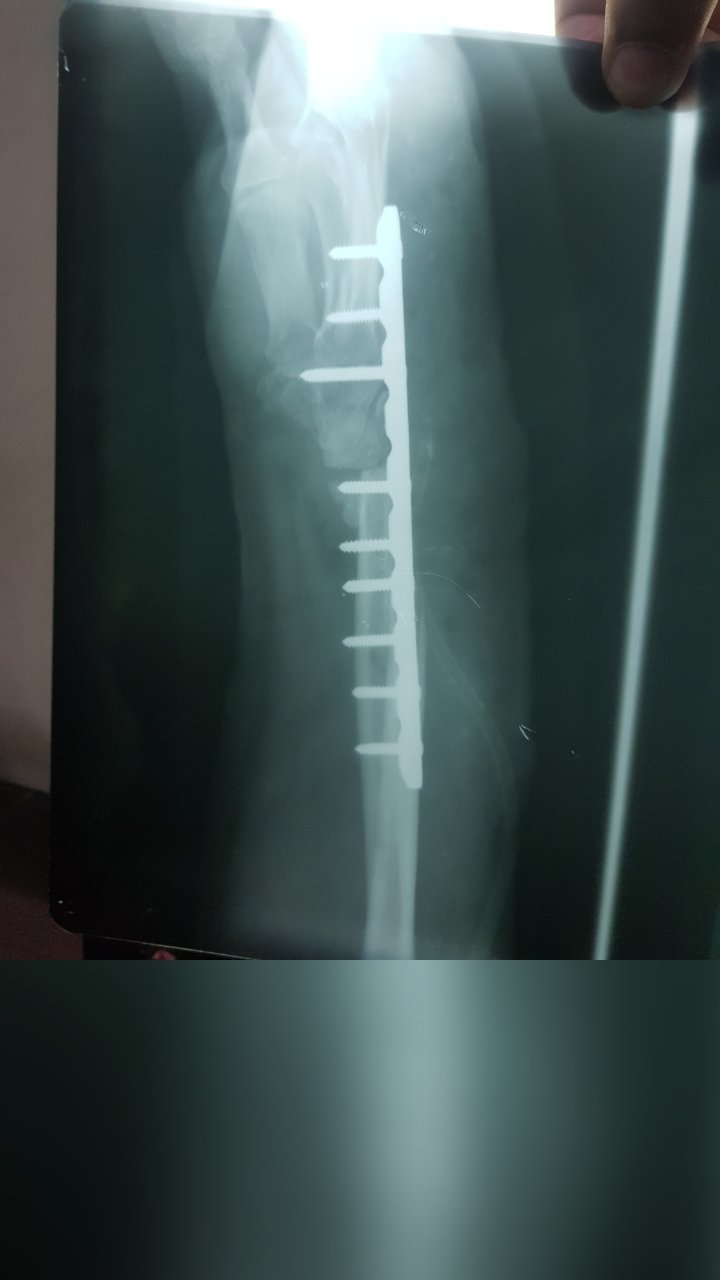

FRACTURE FEMUR SURGERY

FEMUR FRACTURE SURGERY